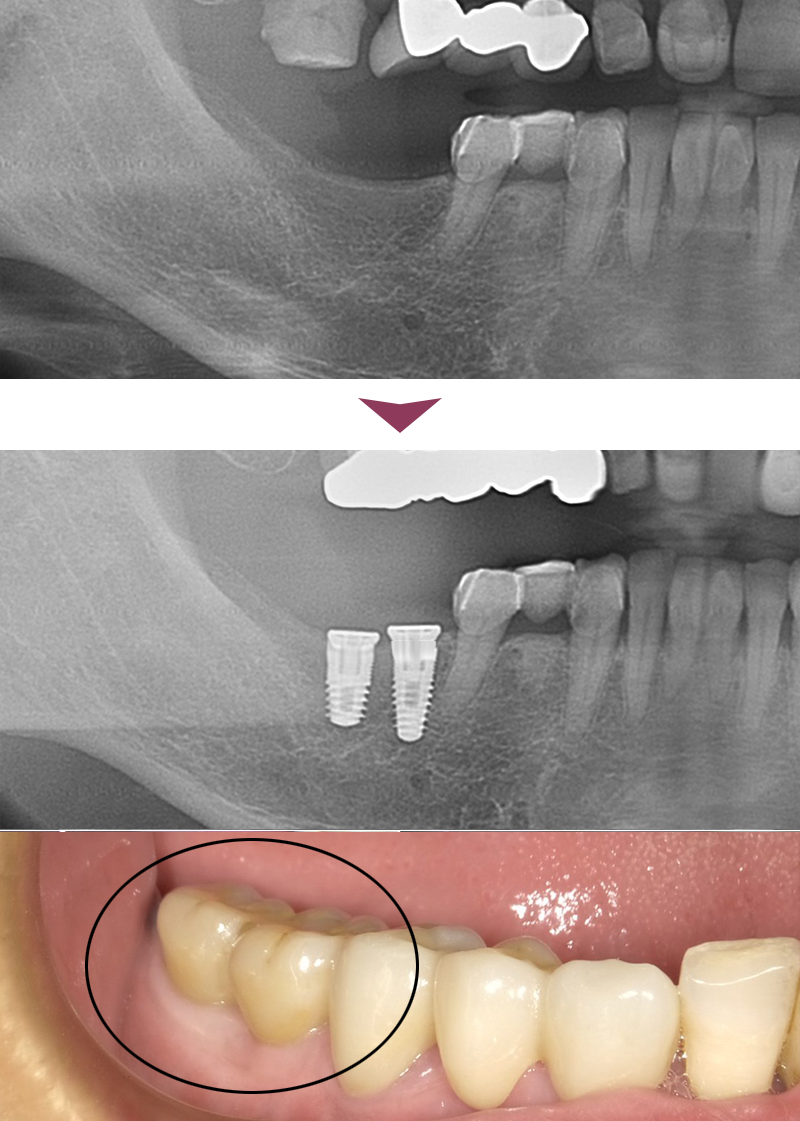

複数本

複数本のケース

インプラント2本埋入のケースです。

主訴 下顎右6番7番の入れ歯を辞めたい

治療内容 下顎右6番7番にインプラントを埋入し、セラミックの上部構造を装着。

治療期間 約4ヶ月

70万円(税込)